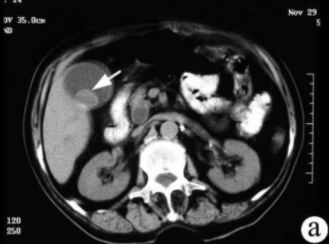

膽囊結石的CT表現:

CT的密度分辨率高,更有利于膽結石的發現。膽石的CT表現與其化學成分密切相關,其CT值與膽固醇含量呈負相關,與膽紅素和鈣含量呈正相關。

CT表現主要有:高密度結石(均勻或不均勻);略高密度結石;等密度結石,與膽汁密度相等平掃不易區分;低密度結石;環狀結石。